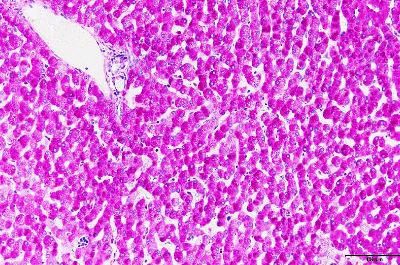

- 【多糖類の染色】

- グリコーゲン、上皮系腺癌、真菌、などの観察に用いられます。

| 過ヨウ素酸シッフ (PAS)反応 →上皮系腺癌、真菌、赤痢アメーバ、など |

細胞内グリコーゲンや腎糸球体基底膜、尿細管基底膜、精巣のアクロソームが赤~赤紫に染まる